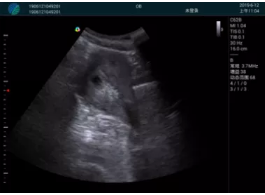

肝內(nèi)血管顯示清晰,血流敏感無外溢

病例二:

甲狀腺囊性結(jié)節(jié),囊壁鈣化,透聲好

甲狀腺囊性占位